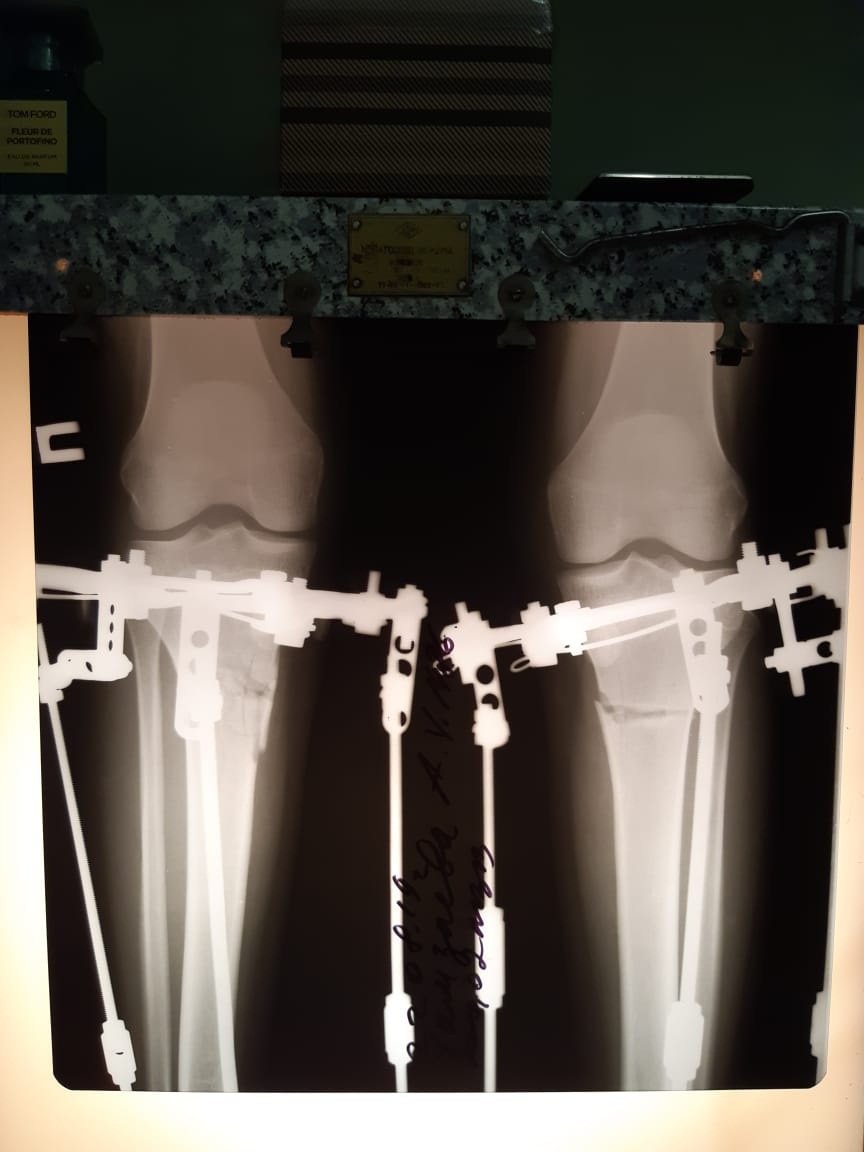

рентген перед снятием аппаратов

Вложения

Дата операции - 30.07.2019г.

Дата снятия аппаратов - 16.11.2019г.

Срок сращения - 106 дней.